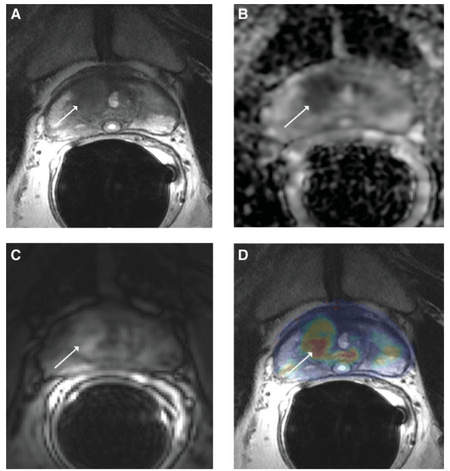

Prostate cancer detection has had huge advancements when coupled with magnetic resonance technology. The American Cancer Society has found that nearly 20% of men will be diagnosed with prostate cancer in their lifetime and early detection is paramount to decrease mortality rates. MR techniques of diffusion weighted and dynamic contrast-enhancement have been integrated into clinical use for their high contrast [8]. Figure 4 shows the effectiveness of MR imaging in locating malignant tumors in the prostate. Figure 4D shows a colored contrast of a prostate tumor in a 57 year old man using a volume transfer constant (Ktrans). The volume transfer constant shows how much volume is being transferred from the blood stream to the tissue [13]. Figures 4A-D show progress in which magnetic resonance imaging is making to better locate and image malignant tumors.